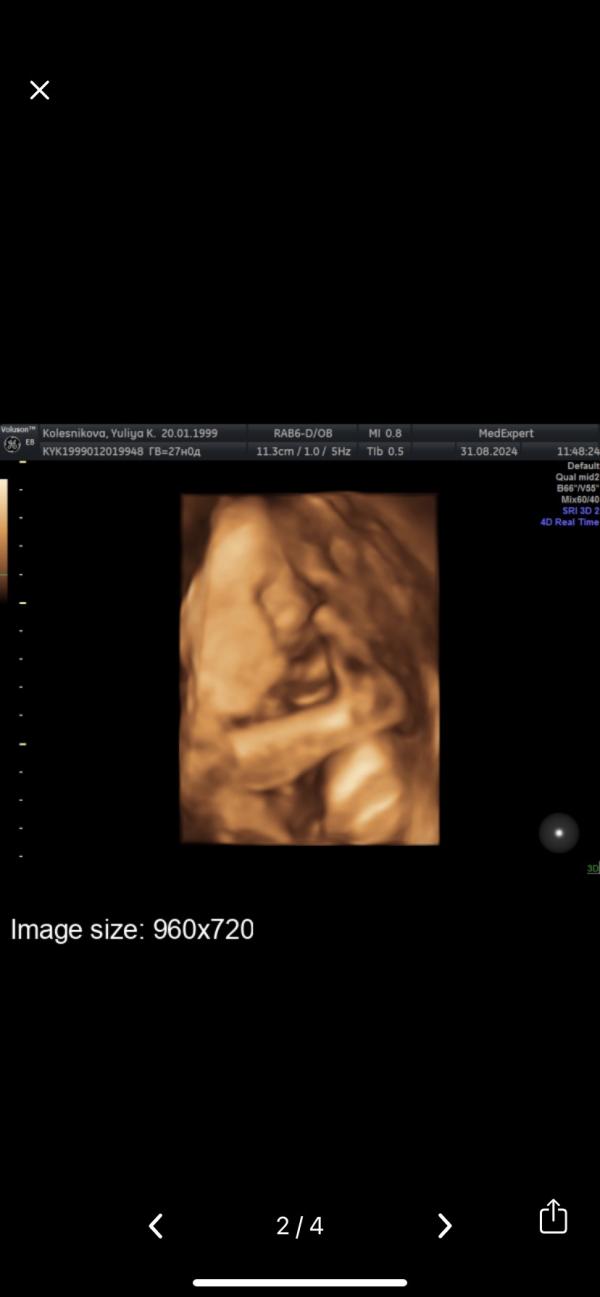

Ну что ж, встретились сегодня с сыном, хотели посмотреть все ли хорошо, как лежит малышок, ну и сделать 3д узи, так как многие рекомендуют делать до 30 недель, а то личико будет сплющено🤪

Крайний раз я ходила на второй скрининг и все время он закрывал лицом руками, сегодня он сделал еще хлеще, закрыл лицо руками и ногами😀🥺

Сказали, что у нас маленький акробат и оказалось лупит сильно все же не руками, а ногами, а жопка у него между моих ребер

По итогу получилось сделать хотя бы одно фото и те...